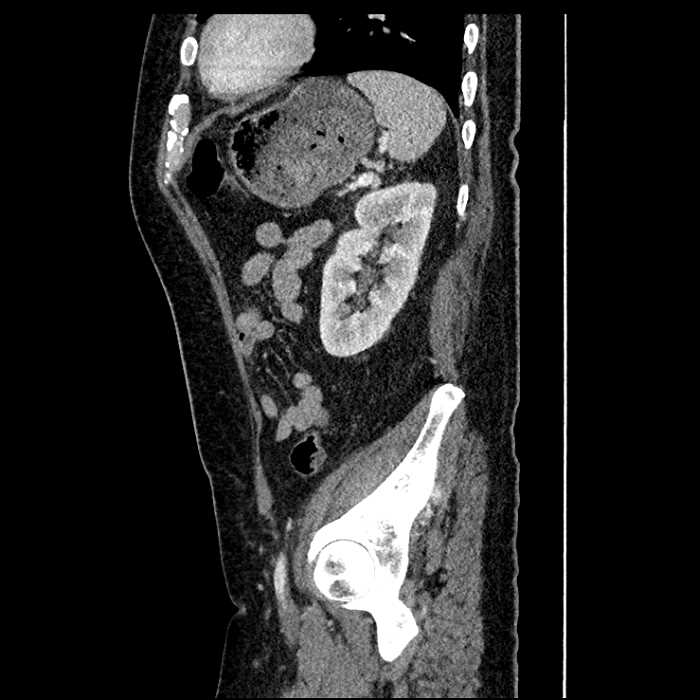

Age: 63

Sex: Male

Indication: Abdominal pain

• Mild mural thickening of a segment of the sigmoid colon with adjacent fat stranding and a 1.5 cm fluid and gas collection along the tip of an inflamed diverticulum

• Loss of the normal fat plane between this collection and adjacent loops of small bowel, which demonstrate mural thickening

• No bowel obstruction

• High grade stenosis of the left common iliac artery, with the left internal and external iliac arteries remaining patent

Acute sigmoid diverticulitis complicated by a small contained perforation and a large abscess in the right hepatic lobe. Additional small subcapsular abscesses along the anterior margin of the left hepatic lobe.

Additionally, loss of the normal fat plane between the peridiverticular collection and adjacent thickened loops of small bowel raises the potential for an enterocolonic fistula.

High grade stenosis of the left common iliac artery. The left external and internal iliac arteries are patent.

Hepatic abscess showing the double target sign with low density internally surrounded by a thin inner enhancing rim (red arrow) and ill-defined outer low density rim (yellow arrow). Blue arrow indicates an internal septation. Red arrows: additional smaller subcapsular abscesses. Red arrow: focal contained perforation associated with diverticulitis.